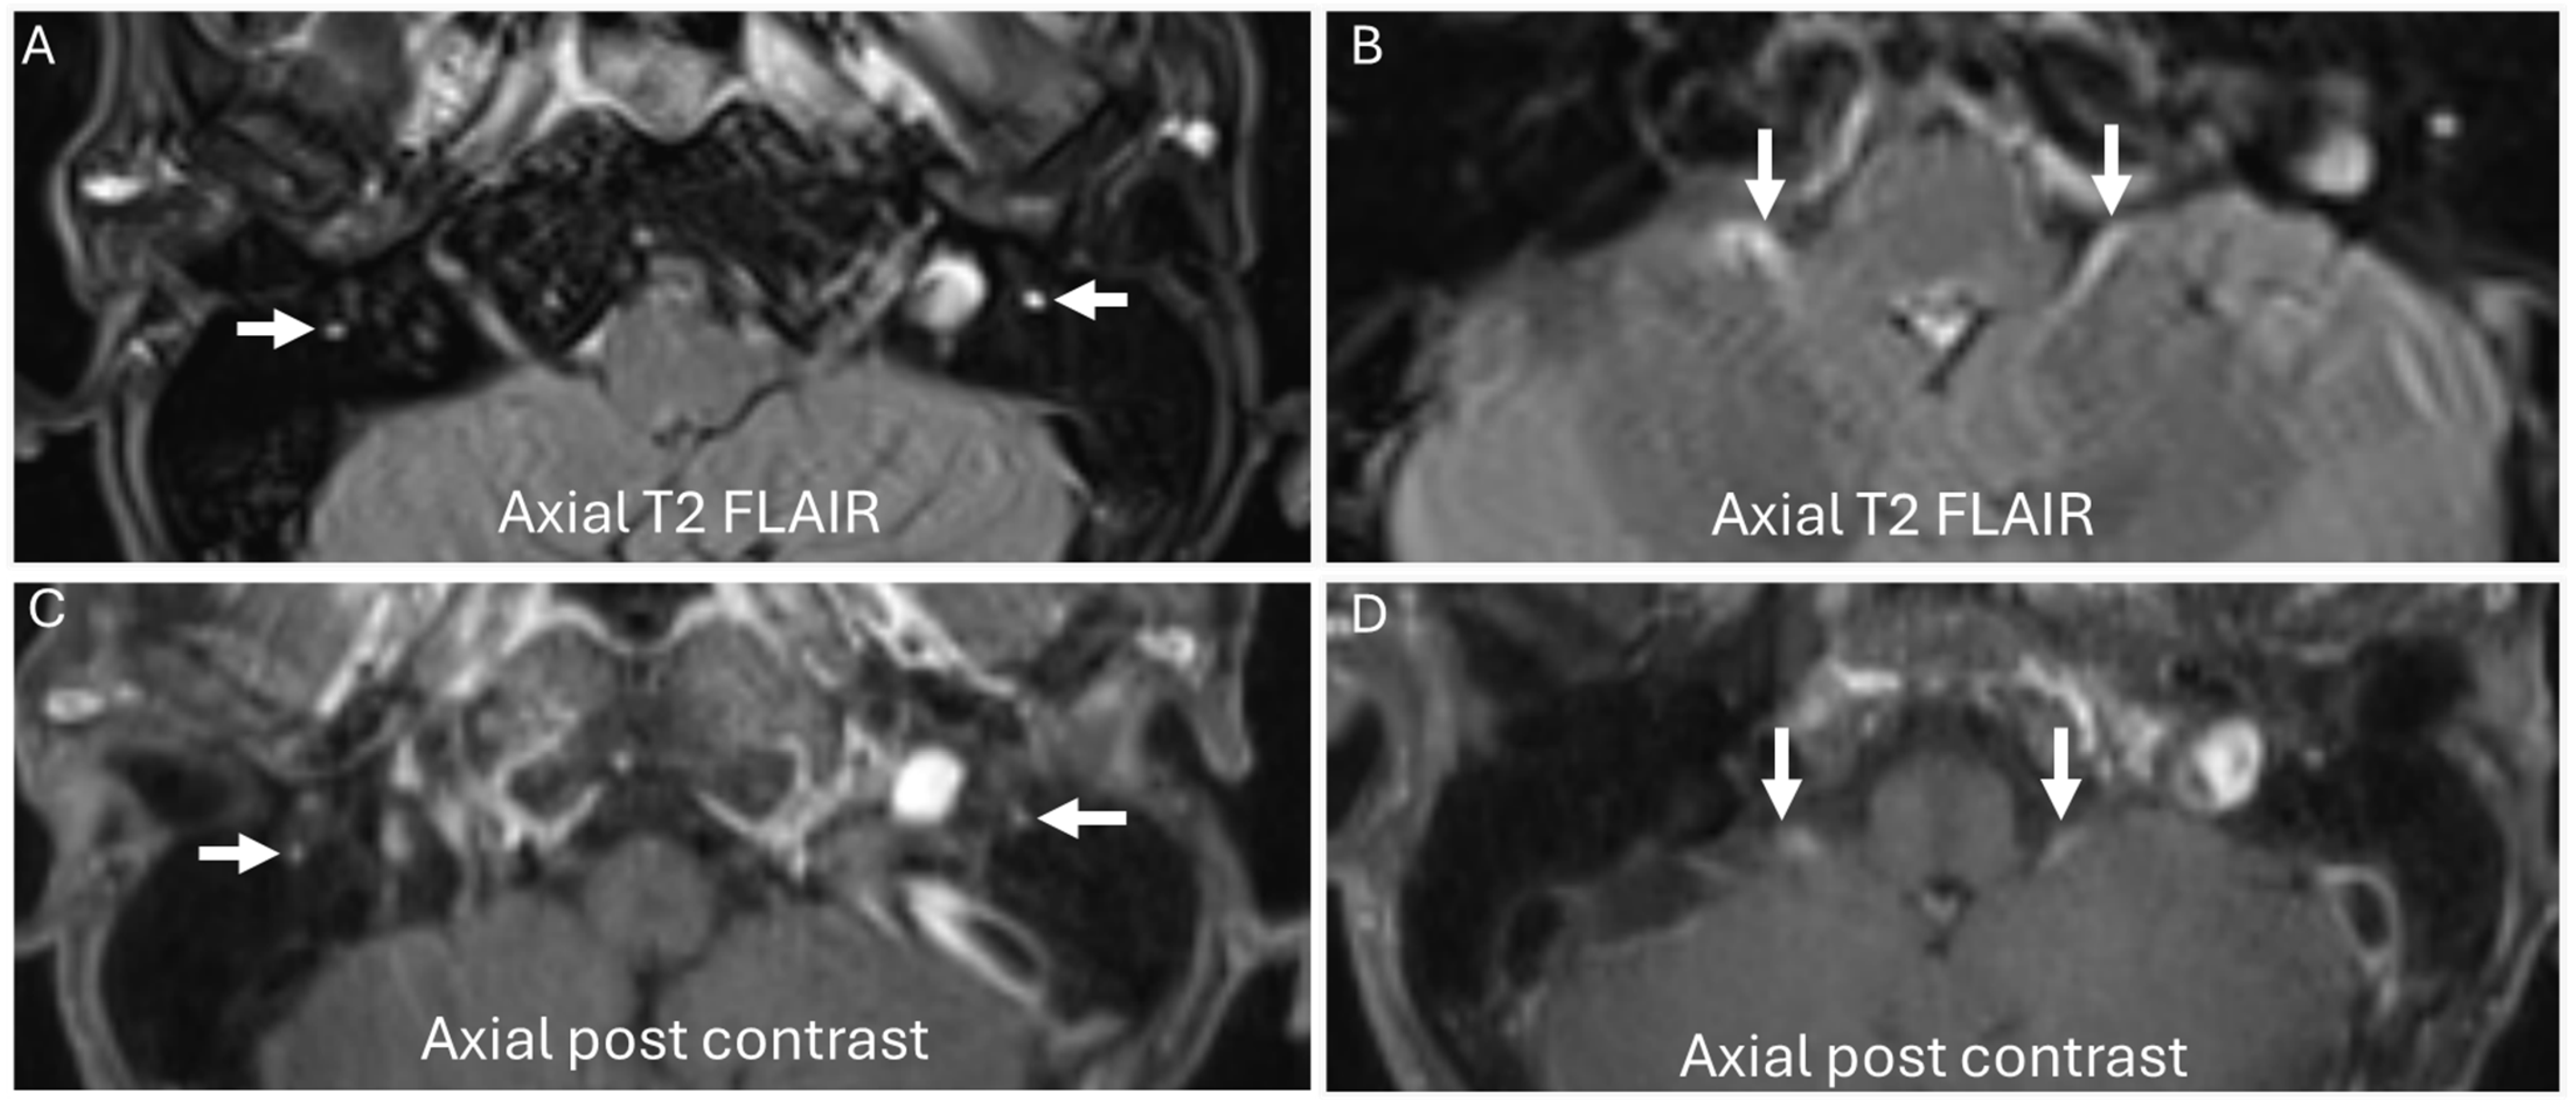

3.4. Chronic Ataxic Neuropathy, Ophthalmoplegia, IgM Paraprotein, Cold Agglutinins, and Disialosyl Antibodies (CANOMAD)

| CANOMAD |